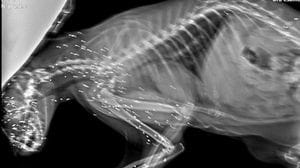

Barbarie ad Airuno: Ciccio, gatto di colonia felina, diventa cieco

Un atto crudele ha reso il micio totalmente dipendente dall’assistenza umana. L’associazione Pro parco nostri amici animali Odv chiede aiuto